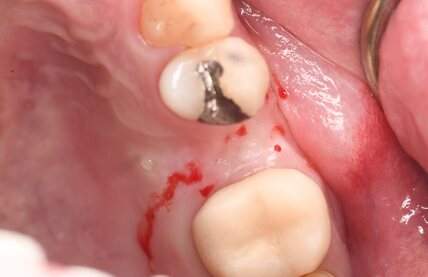

インプラント治療の症例4

口腔内写真

- Befor

- After

| 年齢 | 50代・男性 |

|---|---|

| 主訴 | 部位:左下6番7番 主訴:左下奥歯腫れて痛い。 |

| 治療内容 | 左下6番抜歯、左下6番7番骨造成、インプラント埋入 |

| 治療費 | 合計:1,232,000円 ・内訳 診断料:55,000円 サージカルガイド2本:66,000円 GBR:110,000円×2本 埋入料:165,000円×2本 静脈内鎮静麻酔:77,000円 2次OPE:22,000円×2本 仮歯:55,000円×2本 上部構造(フルジルコニア):165,000円×2本 (2023年1月現在) |

| 治療期間 | 約8ヶ月 |

| 治療方針 | 元々支台歯に負荷がかかりやすいとされている延長ブリッジを抜歯し、1本単体でしっかりかめるようにインプラントを2本埋入した。骨吸収も進んでいたため、※GBR法で骨造成を同時に行った。 治療と並行して、全顎的な歯周病治療も行い、今後は歯周病が進行しないよう、こまめにメンテナンスに通っていただく。 |

| 特記事項 | ※1 GBR・・・骨再生誘導法。骨の高さや厚みを人工骨や人工膜などを使用し再生する方法 |

| 担当者所見 | 6番は歯根分割された被せ物が7番の欠損部との延長ブリッジとされており、強い咬合と歯周病も相まって負荷がかかり動揺し、歯として機能しなくなったため、抜歯となった。 |